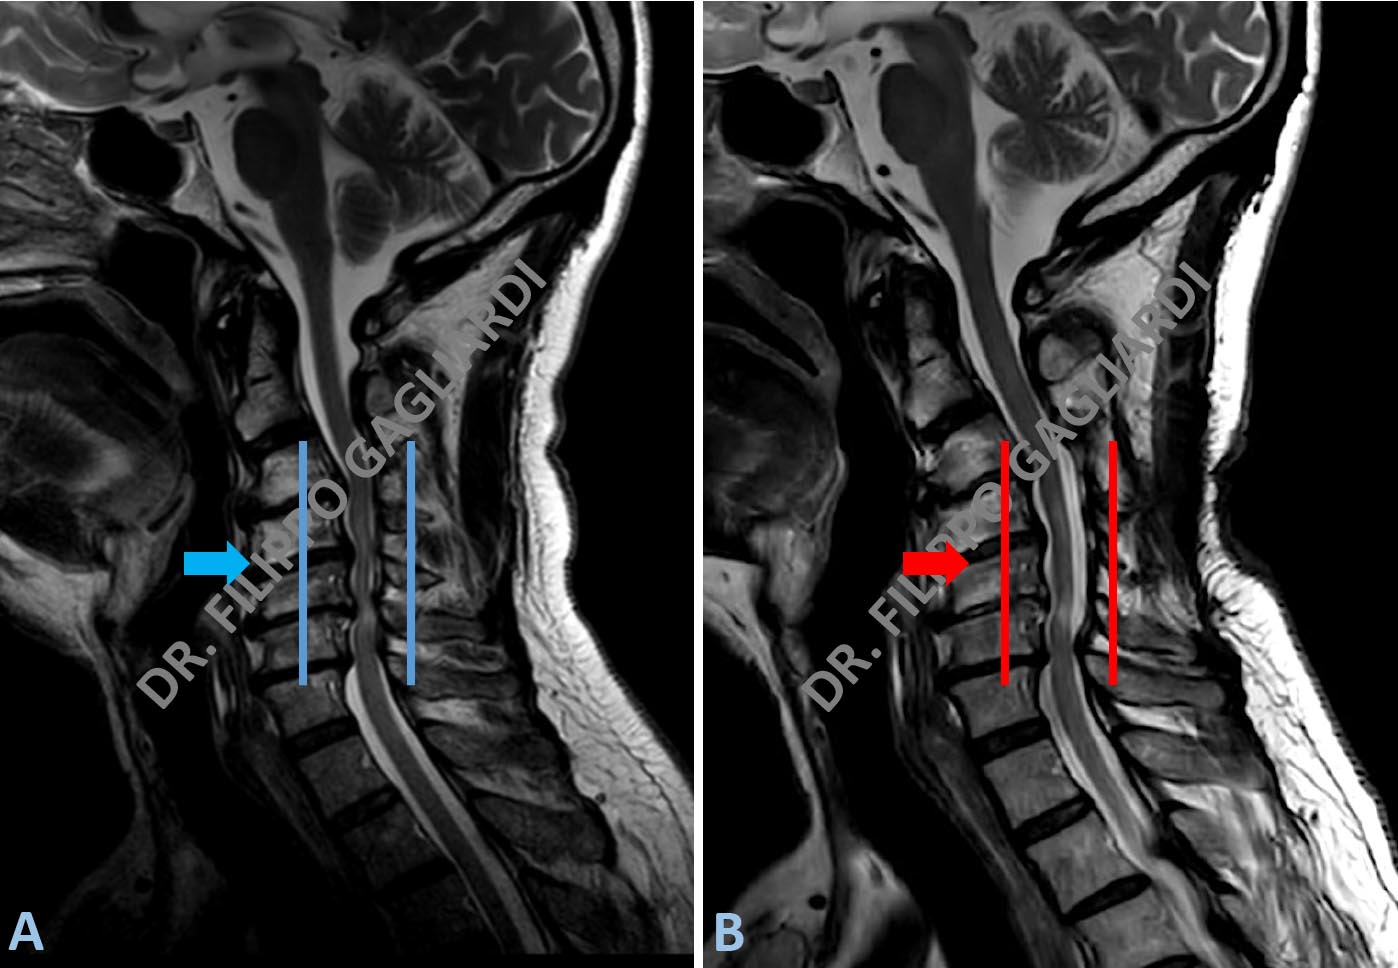

Laminotomia osteoplastica per stenosi cervicale

stenosi del canale cervicale Ulteriore caso di decompressione del canale vertebrale a livello cervicale mediante tecnica di laminotomia osteoplastica. La Figura A mostra la situazione di stenosi (chiusura) del canale prima dell’intervento (freccia azzurra). La Figura B dimostra la situazione dopo l’intervento con apertura del canale e decompressione del midollo spinale (freccia rossa).